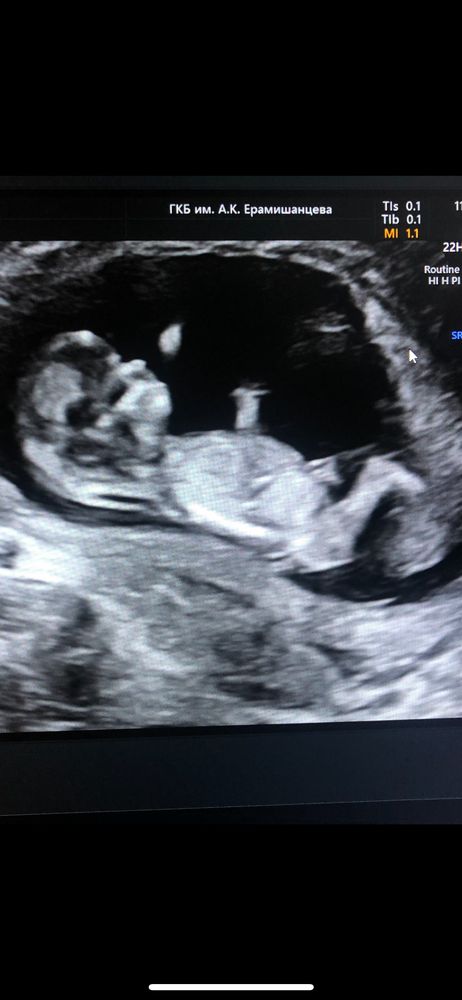

Мальчик или девочка?

Здесь можно только предположить, т.к. бугорка не видно) мне кажется что мальчик💙

Здесь не видно половой бугорок...

Не видно за ножкой) Но склоняюсь к девочке, если смотреть через ножку, то вроде виден половой бугорок и он более горизонтален

Не видно, да и рано)

Пол малыша Пол ребенка на первом скрининге